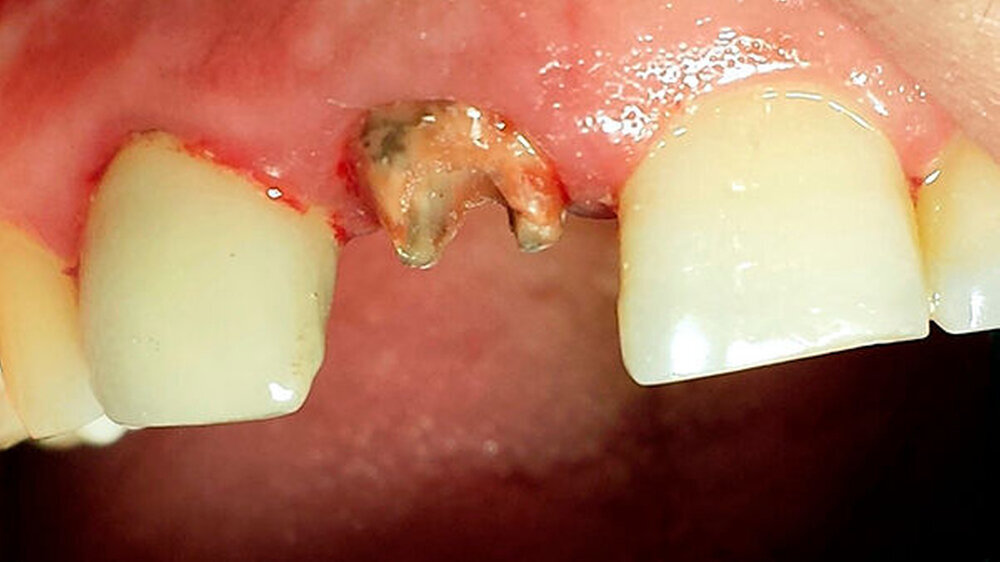

Ein 28-jähriger Mann stellte sich Ende Juli 2015 in der Poliklinik der Universitätszahnklinik Mainz mit herausgefallener Krone an 11 vor (Abbildung 1). Der Patient äußerte den Wunsch der Kronenneuversorgung an 11 und 21 - bei weitestgehend freiliegender Präparationsgrenze mit starker ästhetischer Einschränkung.

Nach klinischer Befundung und Röntgendiagnostik (Abbildung 2) wurde in der Einzelzahnaufnahme eine insuffiziente über das Foramen apicale hinausgebrachte Wurzelkanalfüllung an 11 festgestellt. Zusätzlich bestand eine periapikale Osteolyse. Zahn 12 war ebenfalls endodontisch versorgt, wobei in der Bildgebung kein Nachweis einer radioopaken Füllung des apikalen Kanaldrittels gelang. Es bestand an 12 keine apikale Osteolyse.

Beide Zähne imponierten radiologisch mit weiten apikalen Foramina sowie verkürzten Wurzeln. Auf Nachfrage gab der Patient ein vor circa 20 Jahren stattgefundenes Frontzahntrauma an. Beide Zähne waren klinisch asymptomatisch. Dem Patienten wurden der klinische und röntgenologische Befund erörtert und die Behandlungsoptionen aufgezeigt.